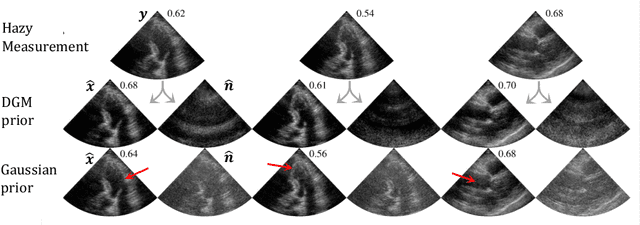

Abstract:Echocardiography has been a prominent tool for the diagnosis of cardiac disease. However, these diagnoses can be heavily impeded by poor image quality. Acoustic clutter emerges due to multipath reflections imposed by layers of skin, subcutaneous fat, and intercostal muscle between the transducer and heart. As a result, haze and other noise artifacts pose a real challenge to cardiac ultrasound imaging. In many cases, especially with difficult-to-image patients such as patients with obesity, a diagnosis from B-Mode ultrasound imaging is effectively rendered unusable, forcing sonographers to resort to contrast-enhanced ultrasound examinations or refer patients to other imaging modalities. Tissue harmonic imaging has been a popular approach to combat haze, but in severe cases is still heavily impacted by haze. Alternatively, denoising algorithms are typically unable to remove highly structured and correlated noise, such as haze. It remains a challenge to accurately describe the statistical properties of structured haze, and develop an inference method to subsequently remove it. Diffusion models have emerged as powerful generative models and have shown their effectiveness in a variety of inverse problems. In this work, we present a joint posterior sampling framework that combines two separate diffusion models to model the distribution of both clean ultrasound and haze in an unsupervised manner. Furthermore, we demonstrate techniques for effectively training diffusion models on radio-frequency ultrasound data and highlight the advantages over image data. Experiments on both \emph{in-vitro} and \emph{in-vivo} cardiac datasets show that the proposed dehazing method effectively removes haze while preserving signals from weakly reflected tissue.